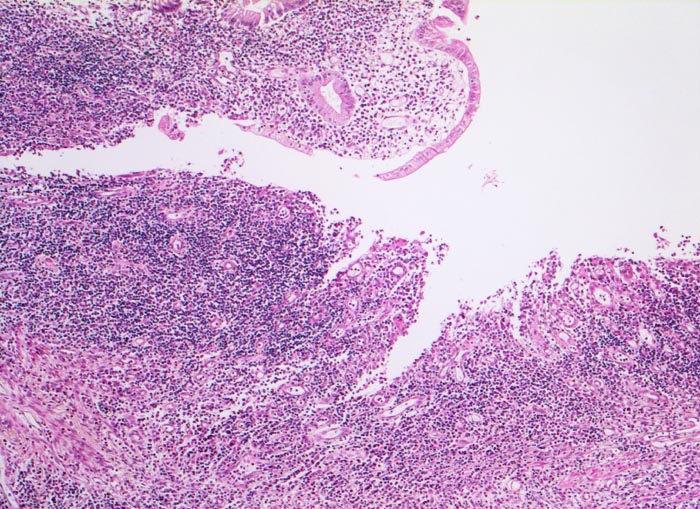

In Biopsien der Darmschleimhaut zeigen sich als Zeichen der Chronizität eine Architekturstörung, reepithelialisierte Schleimhautdefekte und metaplastische Veränderungen. Typisch für den Morbus Crohn sind entzündlich veränderte Schleimhautabschnitte neben weitgehend normaler Schleimhaut. In der Lamina propria findet sich ein verdichtetes gemischtes Infiltrat bestehend aus Lymphozyten, Plasmazellen, Makrophagen, neutrophilen und eosinophilen Granulozyten. Typisch für chronisch entzündliche Darmerkrankungen ist eine basal betonte Lymphoplasmozytose der Lamina propria. Die neutrophilen Granulozyten finden sich herdförmig in der Lamina propria, im Kryptenepithel (Kryptitis) und als Ansammlung in dilatierten Krypten (Kryptenabszess). Erhaltene Schleimhautabschnitte zwischen ulzerierten Arealen und Granulationsgewebe imponieren als entzündliche Pseudopolypen.

• Architekturstörung: Verplumpung und Abflachung der Dünndarmzotten. Verzweigte Krypten.

• Verdichtetes lymphoplasmazelluläres Entzündungsinfiltrat in der Lamina proria.

Neutrophile Granulozyten in der Lamina propria (aktive Entzündung) und Gewebseosinophilie (vermehrte eosinophile Granulozyten in der Lamina propria).